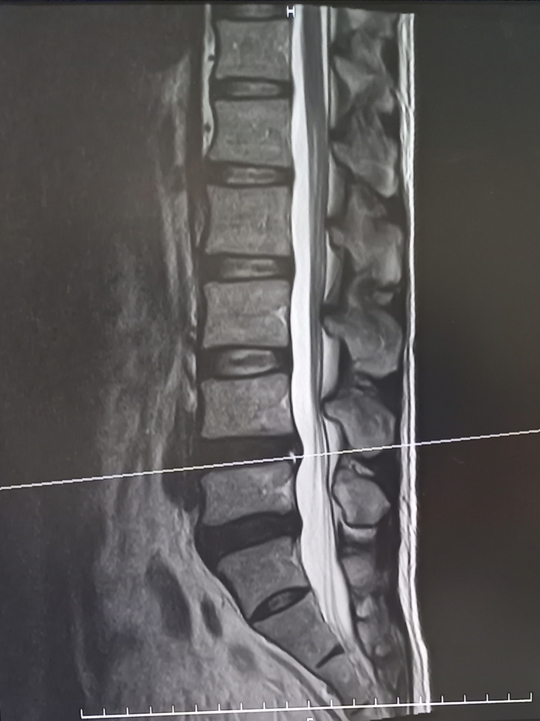

画像検査の役目は骨や椎間板、神経の状態がどのようになっているかを確認することです。

• MRI=椎間板や神経を確認